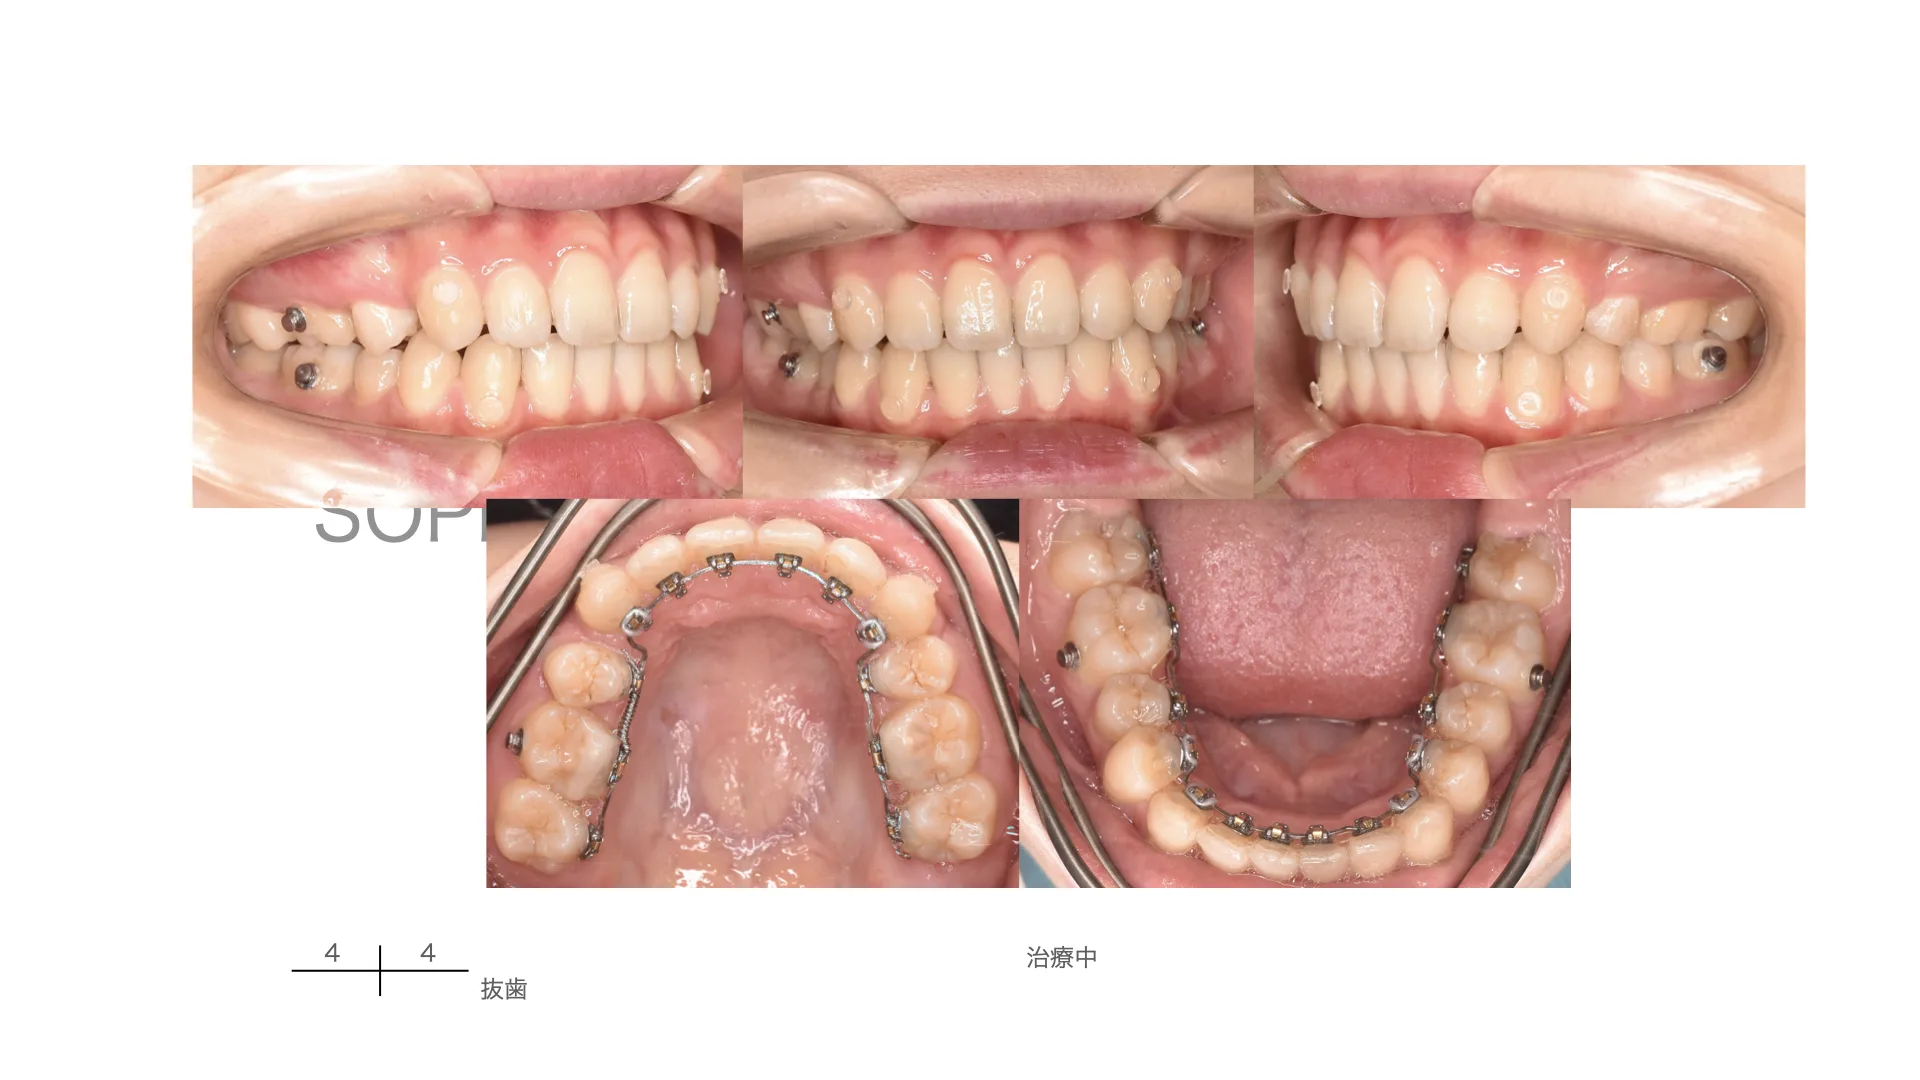

症例 上顎前突 抜歯